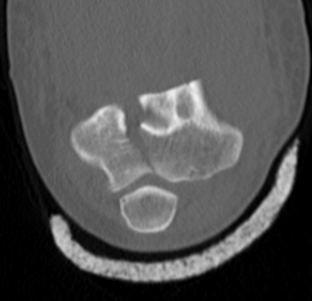

CT scan

OTA / AO Classification

Type A: Extra-articular fracture

Type B: Partial articular fractures

Lateral condyle Medial condyle

Type C: Complete articular fractures